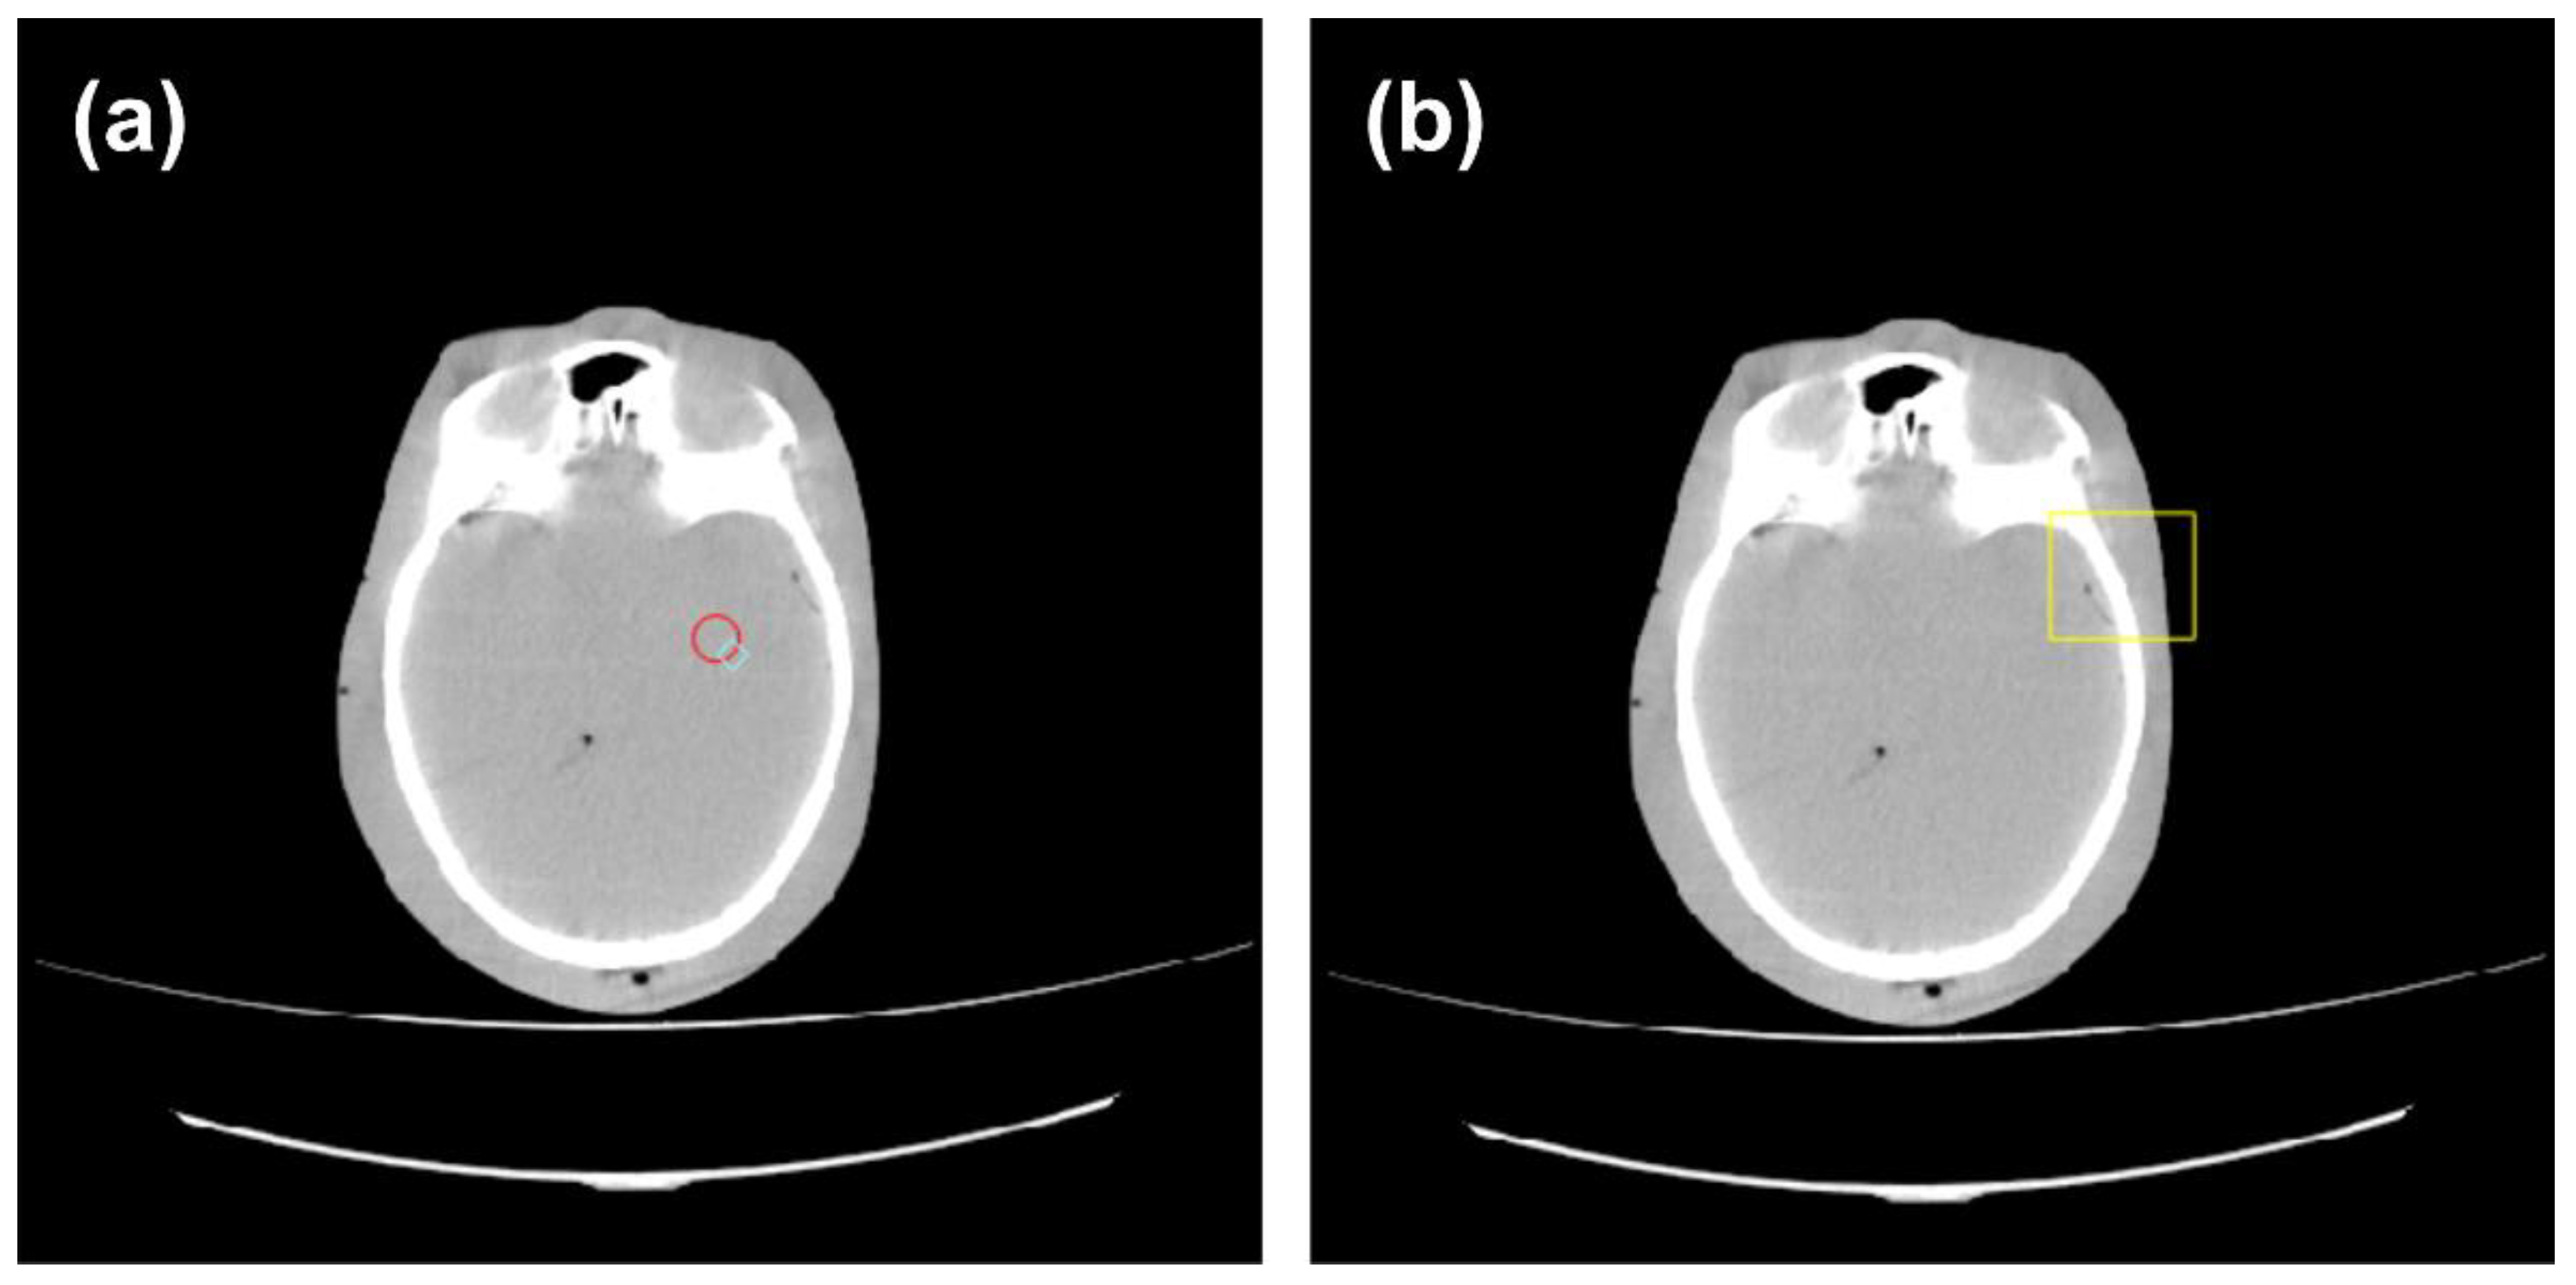

2.4. Implementation of Anthropomorphic Phantom Images

To observe the impact of bilateral filters in clinical scenarios, we obtained anthropomorphic images with scan parameters as shown in Table 2. As before, the bilateral filter was run for 5 iterations on the head anthropomorphic phantom image. The noise was measured using a circular ROI with a radius of 10 mm in the frontal lobe area (Figure 5a). In terms of spatial resolution, we used visual observations on the visible areas of soft tissue, bone, and air (Figure 5b). Comparisons using structural similarity (SSIM) were also carried out to get a more comprehensive description. SSIM was obtained by comparing the filtered image with the original image.

Figure 5.

Anthropomorphic phantom image of the head. (a) ROI for measuring noise, (b) ROI for observing spatial resolution.